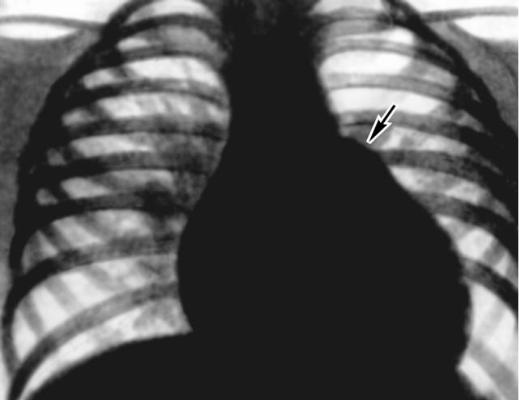

Fig.13"Spherical” configuration of the heart. in a patient with a congenital heart defect. The chest radiograph of a patient with a ventricular septal defect (direct view): the shadow of the heart increased at the expense of both ventricles, visible bulging arc pulmonary trunk (arrow), pulmonary picture in the basal parts of the lungs are strengthened.